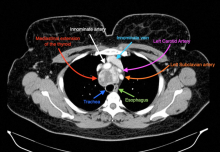

Retrosternal thyroid goiters may occur in the anterior, middle, and posterior mediastinum. Symptomatic retrosternal thyroid goiters are usually amenable to resection via a cervical incision. Sternotomy and thoracotomy are typically employed for retrosternal goiters not amenable to a cervical approach alone. The authors demonstrate a robot-assisted approach for the resection of a retrosternal thyroid goiter in the middle mediastinum.

A patient developed a persistent cough and dyspnea from an enlarged retrosternal thyroid. A combined cervical and right robot-assisted approach for resecting the retrosternal thyroid was undertaken. The patient was positioned in the supine position with a right bump, in preparation for a possible right robot-assisted approach. The cervical approach was met with difficulties in dissecting the mediastinal extension of the enlarged thyroid. Three robotic ports and one assistant port were placed into the right chest. The robot was docked, and the mediastinal extension of the thyroid was released. The specimen was extracted from the cervical incision.